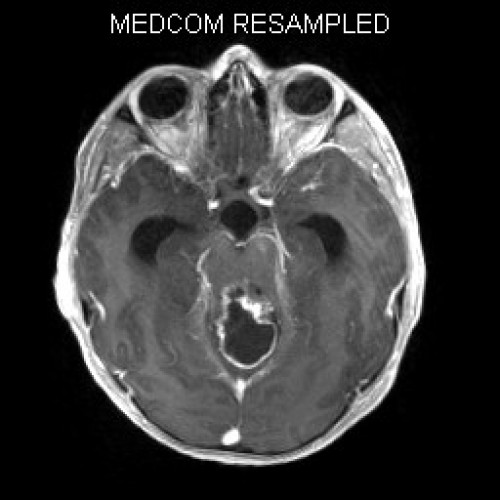

Müdigkeit und schlechte Noten

Fall-ID: 592

ICD: C75.3

ICD: G91.9

12-jähriger Junge. Die Eltern werden zu einem Gespräch bei der Klassenlehrerin gebeten, weil ihr Sohn sehr unaufmerksam geworden sei und seine Leistungen in der Schule bedenklich abgenommen hätten. Er droht das Klassenziel der 6. Klasse nicht zu erreichen.

Den Eltern war seit längerer Zeit bereits aufgefallen, dass sich ihr Sohn nach der Schule am liebsten ins Bett lege, um für eine Stunde einen Mittagsschlaf zu halten.